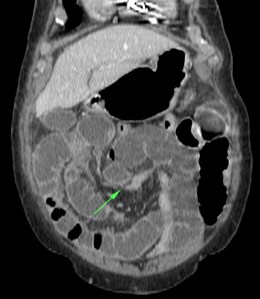

Se realiza TC de abdomen en vacío y con contraste en fase portal:

Estamos ante un cuadro de isquemia intestinal en un paciente con bajo gasto cardiaco con afectación principal de asas intestino delgado, territorio vacularizado por la arteria mesentérica superior.

Flecha roja: colateral que repermeabiliza la AMS.